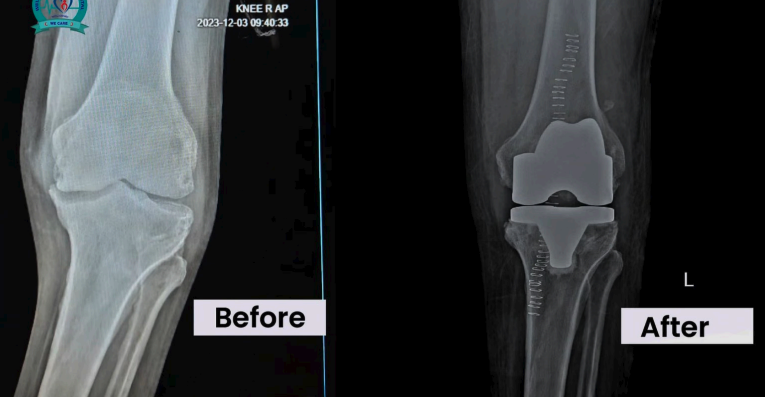

Orthopedic & Trauma Outreach Program. First Hip & Knee Replacement Program done in Somalia for nominal fees.

Professor of Trauma & Orthopedics and Consultant Orthopedic & traumatology’s Surgeon